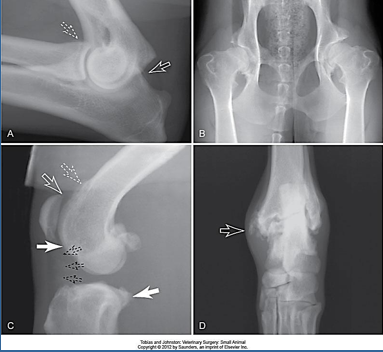

What are some radiographic signs of arthritis?

What are the arrows pointing to?

Osteophytes